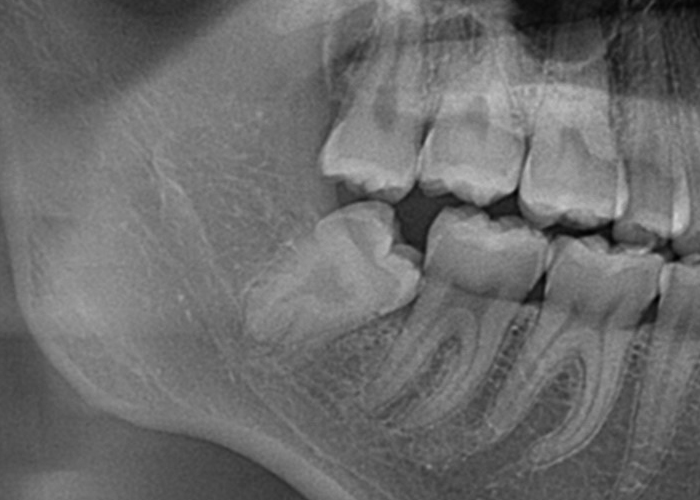

骨性完全埋伏智歯(骨に完全に埋まっている)

この場合も親知らずは通常、レントゲンやCTスキャンなどの画像検査でのみ確認できます。

完全埋伏の親知らずは、周囲の組織に直接的な問題を引き起こさない場合もありますが、将来的に問題を引き起こす可能性があります。

そのため、定期的な口腔検診や画像検査が重要です。

もしこのような歯が抜歯が必要となった場合は近隣口腔外科への紹介をする場合があります。